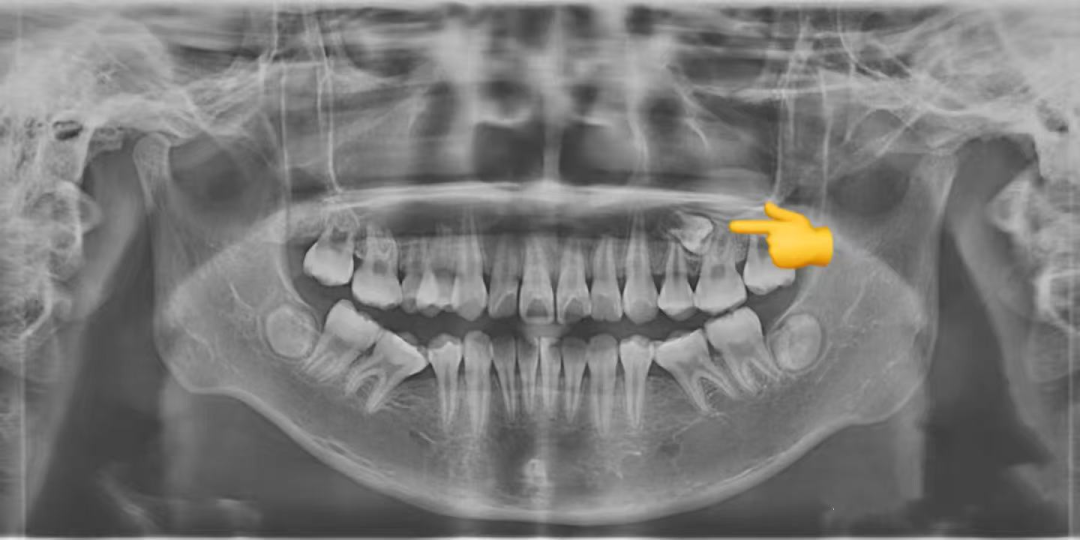

简单来说,埋伏牙就是牙齿在萌出的过程中,因为各种原因没能顺利长到口腔里,而是 “藏” 在了颌骨里面。这就好比一颗种子被种下去后,却始终没有破土而出,默默待在土壤里一样。

值得庆幸的是,随着多学科联合治疗的开展以及正畸技术的不断发展与完善,更多的上颌前牙埋伏阻生齿得以矫治和保留。通过正畸 - 外科联合牵引助萌复杂埋伏阻生牙的方法,往往能获得良好的效果,帮助患儿健康自信地成长。

如果大家怀疑自己有埋伏牙,一定要及时去正规的口腔医院进行检查。通常情况下,拍个 X 光片就能清楚地看到牙齿的情况了。